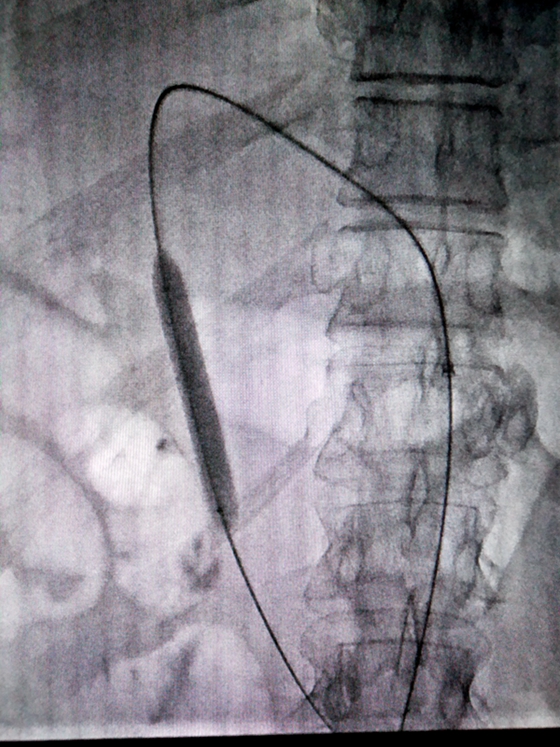

球囊扩张